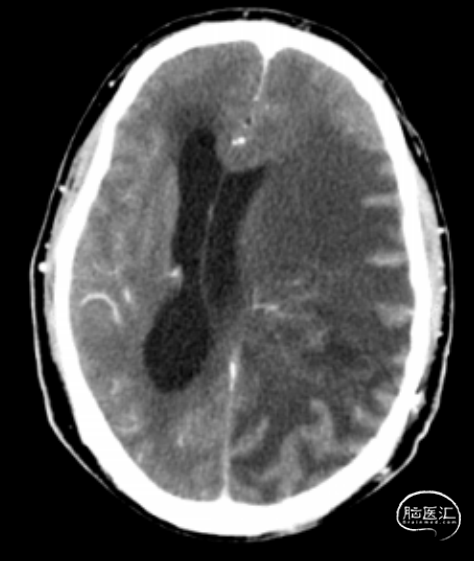

影像学资料

男性患者,51岁,肿瘤切除后接受放化疗以及TTFields 术后病理检测及分子基因检测显示为胶质母细胞瘤(IDH野生,TERT突变),预后约11.3个月;MGMT无甲基化组( 即甲基化均值<10% ),mPFS为7.2个月,mOS为13.4个月 患者术后约1月开始进行同步放化疗,同步放化疗期间接受TTFields;期间出现额叶转移、对侧新发肿瘤、额叶新生肿瘤以及右侧脑室旁新生肿瘤等4次肿瘤进展,1次癫痫;根据患者具体情况动态调整放靶向药物以及免疫疗法药物,调整TTFields佩戴时间 远端进展的出现可能有:1.TTFields根据肿瘤位置进行个体化定位,TTFields强度集中于肿瘤发生位置,以达到最佳治疗效果;2.在出现远处肿瘤复发脑区,放射野未覆盖或覆盖剂量不足;3.使用TTFields的患者生存时间延长,所以更有机会观察到远端转移的发生 提高患者的依从性是TTFields改善胶质母细胞瘤生存的独立预后因素;TTFields期间,因皮疹/癫痫暂停TTFields4次,后经药物处理后病情好转并逐渐稳定

这例患者在外院手术后转来我院,从早期治疗期间的MR结果来看,肿瘤的恶性程度极高。这与患者的肿瘤基因检测的不良预后分子特征相符:IDH野生型,TERT突变,MGMT启动子无甲基化。因此,在早期即给与了积极的综合治疗。按照NCCN指南,早期放疗期间即用上TTFields,放疗结束即按照基因检测到的突变靶点以及其相关案例报道,探索性应用靶向治疗,给予早期干预。但是,靶向药物的副作用间接减少了TTFields的使用时间,影响疗效。因此,在使用TTFields联用其他治疗时,特别需警惕选用容易引起皮疹的药物,以免影响TTFields的疗效。

这是一例左顶叶原发性胶质母细胞瘤的患者,各项分子指标提示预后很差:1.IDH野生型;2.TERT启动子突变;3.MGMT非甲基化。从患者后续的治疗也可以看到治疗过程曲折,疗效反复,多次复发并出现颅内多灶播散。在整个治疗过程中,临床医生根据最新的循证医学证据,积极尝试了靶向、免疫等联合治疗方案,最终达到21个月的OS,优于历史数据的中位值。